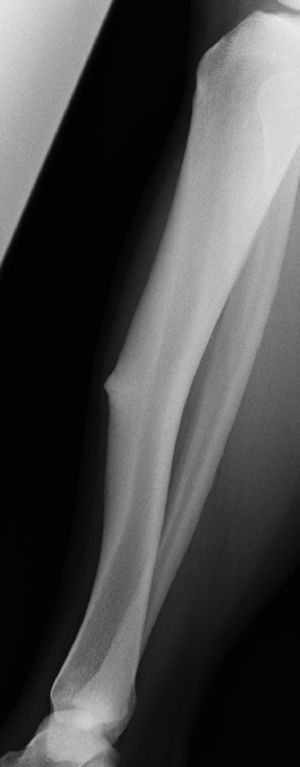

El grosor de las corticales y la estrechez del canal endomedular obligaron a tratar con sistema de placas bloqueadas (LCP de Synthes®) en lugar del enclavado endomedular que utilizamos en nuestro centro como tratamiento de primera elección para las fracturas de tercio medio de tibia. La evolución de la fractura fue la consolidación, aunque requirió más tiempo del normal para la consolidación completa de la fractura. En la exploración física del paciente se evidenció deformidad en la pierna afectada y tumoración sólida en el tercio medio de la pierna contralateral (fig. 2), correspondiente a un engrosamiento de la cortical anterior de la tibia, consecuencia de una fatiga crónica.

Al año del suceso el paciente sufrió una fractura en la otra pierna que requirió el mismo tratamiento quirúrgico.